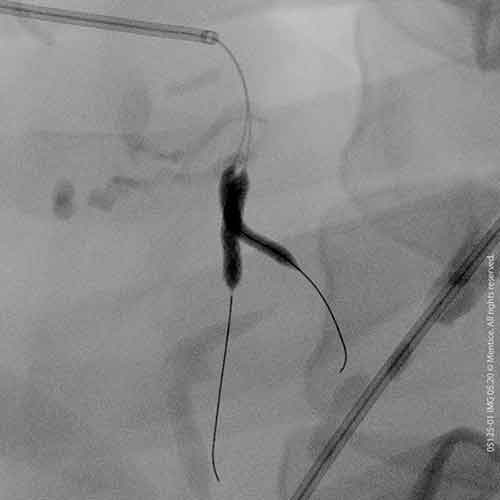

Virtual Reality simulators for image-guided interventional therapies

Our anatomical software physics engine, combined with haptic-enabled hardware solutions, creates the optimal environment for procedural adoption, proficiency-based training, patient-specific simulation, and objective skills assessment. Over 350 development years of engineering have created the most advanced IGIT simulation solutions on the market.

Over 2000+ systems delivered worldwide that cover fluoro & echo based learning solutions from head to toe for both Healthcare Professionals and the MedTech Industry.